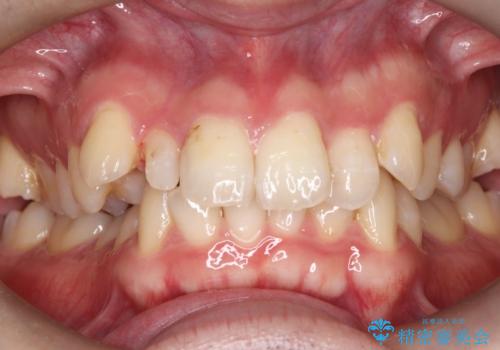

- 主訴:右上の前歯が何しなくても痛い

右上2番の歯に自発痛を認め、症状や歯髄診・レントゲン像から不可逆性歯髄炎と診断し、精密根管治療から歯冠補綴まで行うこととなりました。

初診時に歯髄診断を行い、不可逆性歯髄炎と診断し抜髄から補綴修復までの流れを説明し、精密根管治療、ファイバ-コア築造、オールセラミッククラウン(St)修復を行うこととしました。